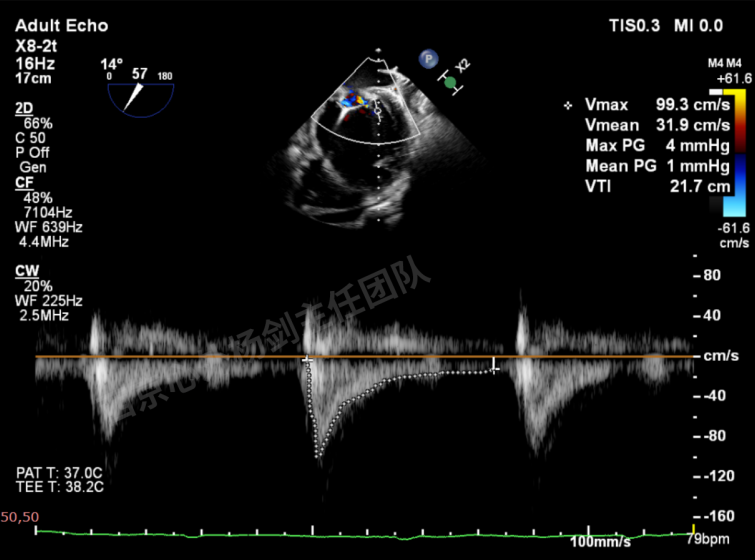

二尖瓣平均跨瓣压差1mmHg

释放后评估,反流降至1+,组织桥稳定

M-TEER术后三尖瓣反流减轻